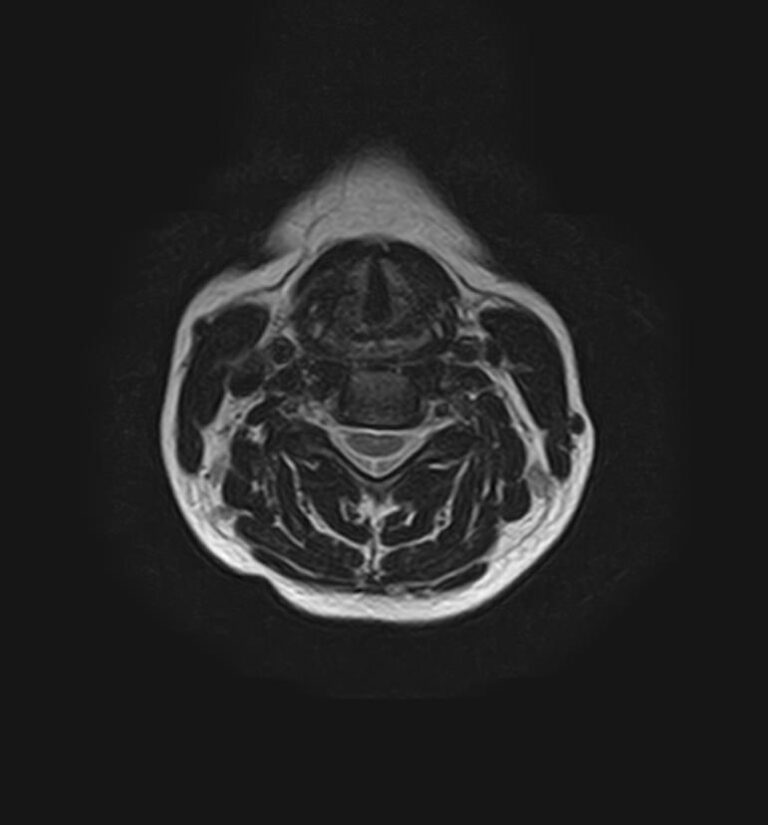

Для того, чтобы оценить состояние шейных позвонков с прилегающими тканями и одновременно визуализировать плечевой сустав, в нашей клинике выполняется комплексное обследование, включающее два протокола: МРТ шейного отдела позвоночника и МРТ плечевого сустава.

Метод МРТ позволяет оценить состояние всех анатомических областей шейного отдела позвоночника: костную структуру позвонков, спинной мозг с отходящими от него нервными корешками и окружающие мягкие ткани. Протокол обследования плечевого сустава включает оценку костной структуры, суставной капсулы, полости сустава с выстилающей его синовиальной оболочкой, связок, сухожилий, мышц и окружающих мягких тканей.

В клинике «Доступная медицина» исследование проводится на современном высокопольном томографе закрытого типа TOSHIBA VANTAGE TITAN 1,5 Тесла с превосходной  разрешающей способностью, которая обеспечивается высокой индукцией магнитного поля. Аппарат выполняет сканирование послойно в различных плоскостях и на основе этого создает 3D-изображения с высочайшей точностью и достоверностью, что позволяет эффективно ставить диагноз и назначать необходимое лечение.